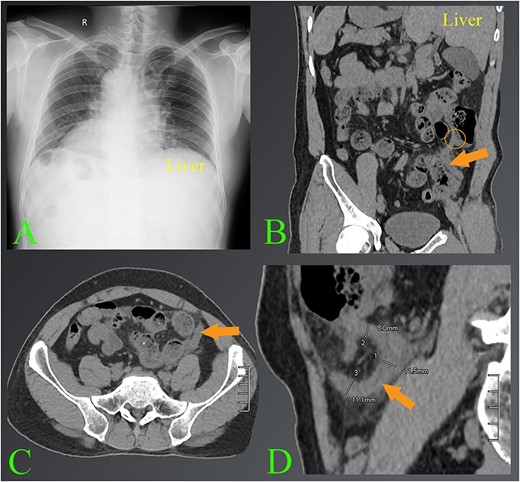

A 42-year-old male admitted to the hospital with dull abdominal pain that had persisted for the previous 10 h. The patient stated that the pain started in the epigastrium and then spread to the left iliac fossa. Accompanying symptoms were nausea and shivering fever. The patient had a known history of organ reversal. The clinician suspected acute appendicitis, ordered routine tests, chest radiograph and abdominal ultrasound immediately afterwards. Complete blood count showed an elevated white blood cell count of about 16 000/mL. The chest radiograph showed the existence of dextrocardia (Fig. 1A). The ultrasound results showed that a sonographer’s attempt was made to find the cause of abdominal pain in the left iliac fossa, but because the patient had a stiff abdomen, the appendix was not detected. The patient underwent a CT scan shortly thereafter. CT images confirmed the diagnosis of the left-sided acute appendicitis with situs inversus totalis (Fig. 1B–D). After carefully assessing the position of the appendix relative to the patient’s condition, a laparoscopic appendectomy was conducted.

The images of appendicitis in a patient with situs inversus. (A) Chest X-ray of the chest shows that the heart is on the right side. (B–D) The CT images show the left-sided acute appendicitis with surrounding fatty infiltration (arrows). The root of the appendix located high in the left lumbar position is also seen (circle). Note where the liver is located on the left side.